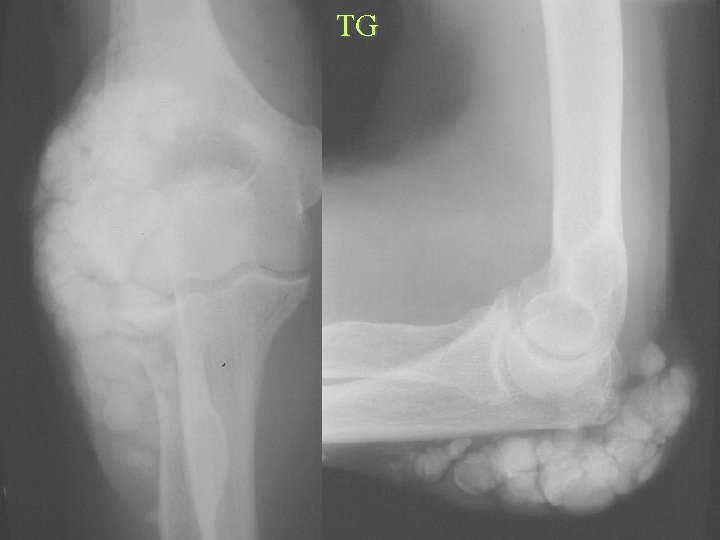

Calcification By Shape Tumoral calcinosis DDX • • • Idiopathic Renal osteodystrophy Gout Hypervitaminosis D Hyperparathyroidism Collagen vascular Disease

ITC

CAPD

TG